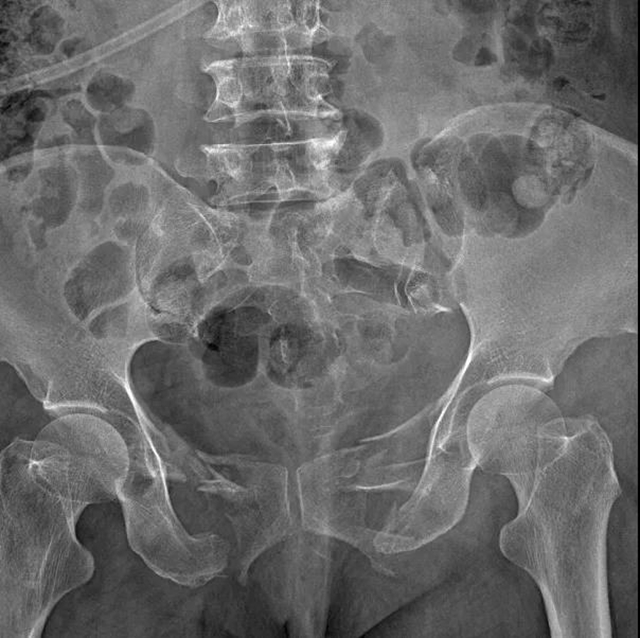

经详细检查,两位阿姨均被确诊为骨盆多发骨折,耻骨上下支骨折,髂骨骨折,骶髂关节分离。

什么是耻骨上下支骨折?

陈文辉表示,耻骨上下支骨折是骨盆骨折的一种。骨盆骨折是指骨盆骨性结构由于外力因素出现的骨质完整性破坏,出现骨盆的挤压变形等。骨盆骨折出血量大、止血难度大,多在1000毫升以上,加之容易合并膀胱、输尿管等盆腔脏器损伤,因此一直是骨科治疗的重点和难点。